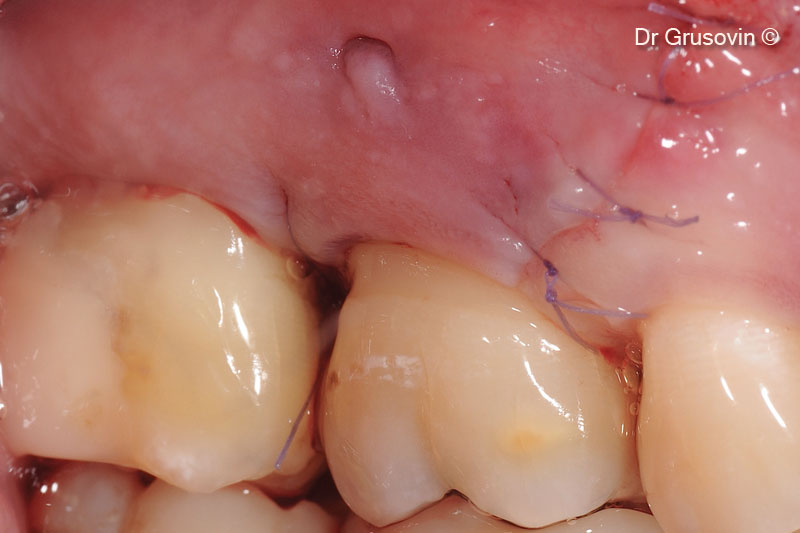

7. Closure of papilla preservation flap